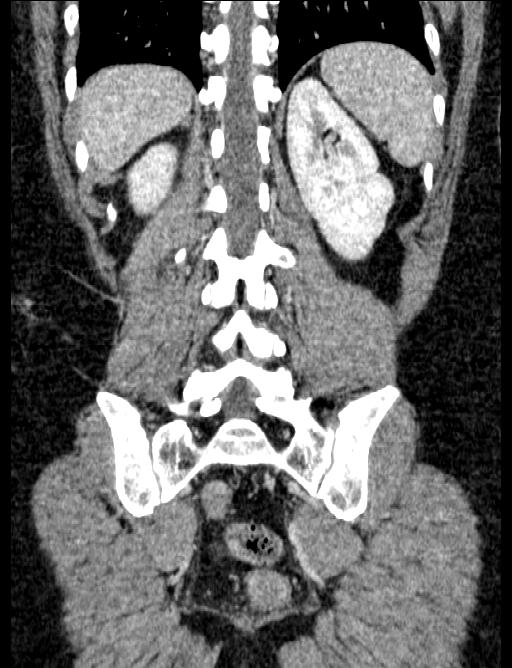

2010